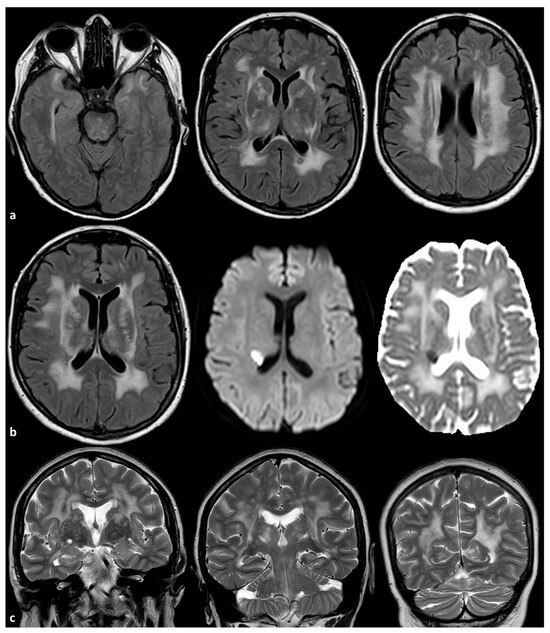

- Duering, M.; Biessels, G.J.; Brodtmann, A.; Chen, C.; Cordonnier, C.; de Leeuw, F.-E.; Debette, S.; Frayne, R.; Jouvent, E.; Rost, N.S.; et al. Neuroimaging standards for research into small vessel disease—Advances since 2013. Lancet Neurol. 2023, 22, 602–618. [Google Scholar] [CrossRef]

- Uemura, M.; Hatano, Y.; Nozaki, H.; Ando, S.; Kondo, H.; Hanazono, A.; Iwanaga, A.; Murota, H.; Osakada, Y.; Osaki, M.; et al. High frequency of HTRA1 and ABCC6 mutations in Japanese patients with adult-onset cerebral small vessel disease. J. Neurol. Neurosurg. Psychiatry 2022, 94, 74–81. [Google Scholar] [CrossRef] [PubMed]

- De Vilder, E.Y.; Cardoen, S.; Hosen, M.J.; Le Saux, O.; De Zaeytijd, J.; Leroy, B.P.; De Reuck, J.; Coucke, P.J.; De Paepe, A.; Hemelsoet, D.; et al. Pathogenic variants in the ABCC6 gene are associated with an increased risk for ischemic stroke. Brain Pathol. 2018, 28, 822–831. [Google Scholar] [CrossRef]

- Kauw, F.; Kranenburg, G.; Kappelle, L.J.; Hendrikse, J.; Koek, H.L.; Visseren, F.L.J.; Mali, W.P.T.; de Jong, P.A.; Spiering, W. Cerebral disease in a nationwide Dutch pseudoxanthoma elasticum cohort with a systematic review of the literature. J. Neurol. Sci. 2017, 15, 167–172. [Google Scholar] [CrossRef]

- Bartstra, J.W.; van den Beukel, T.; Kranenburg, G.; Geurts, L.J.; den Harder, A.M.; Witkamp, T.; Wolterink, J.M.; Zwanenburg, J.J.M.; van Valen, E.; Koek, H.L.; et al. Increased Intracranial Arterial Pulsatility and Micro-vascular Brain Damage in Pseudoxanthoma Elasticum. AJNR Am. J. Neuroradiol. 2024, 45, 386–392. [Google Scholar] [CrossRef]